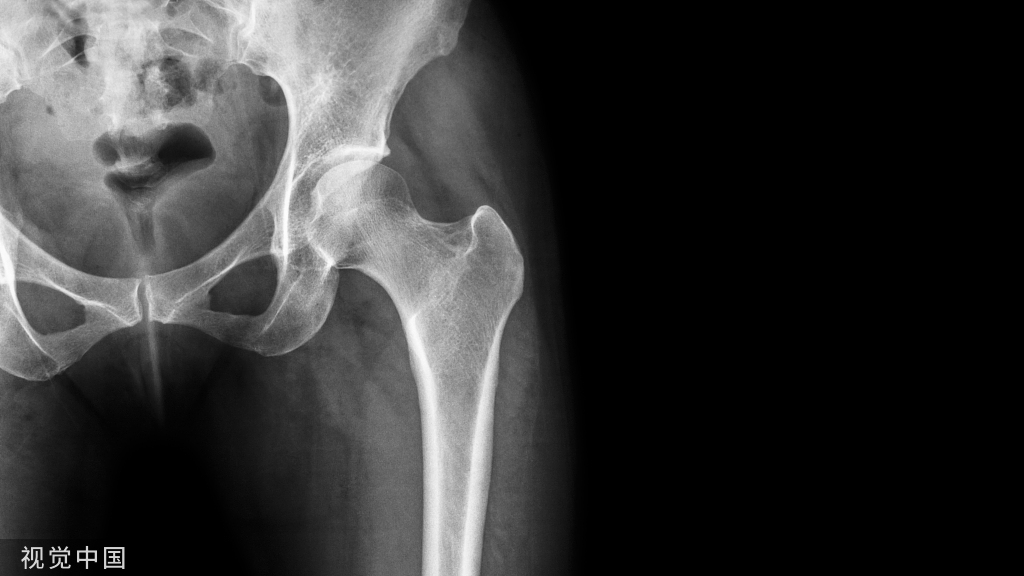

骨质疏松症是全身骨骼成分减少的一种现象,就是破骨细胞把骨头吃掉了,主要表现为骨组织内单位体积中骨量减少,由于骨质疏松症病程缓慢而常被忽略,直到发生骨折,被称为寂静的杀手。

如何预防和治疗骨质疏松症,先把这幅图搬出来。